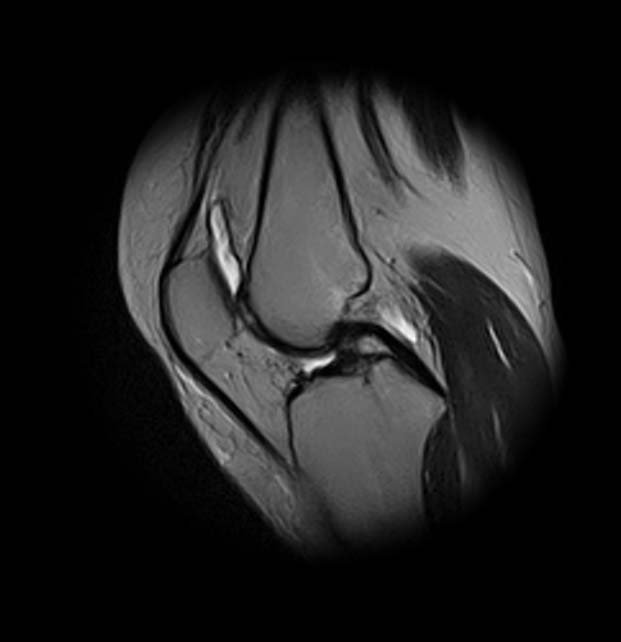

добрый день! Не очень понятен принцип, по которому отбирались снимки МРТ. Большинство из них не показательны. Вижу пока только повреждение хряща на феморопателлярной поверхности. Хлтелось бы посмотреть диск целиком

На снимках повреждений наружного мениска не вижу и кисты мениска не вижу. Есть повреждение хряща на передней поверхности внутреннего мыщелка бедра. Вполне может оказаться, что повреждение лоскутное. А какая консервативная терапия проводилась?